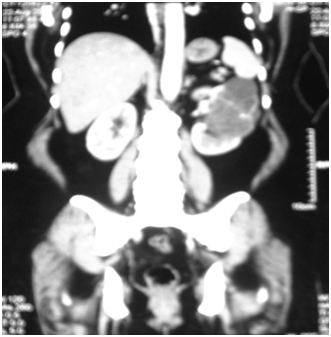

A 53years old obese woman presented with vague abdominal pain of one year duration. Physical examination was unremarkable. Ultra sonography of the whole abdomen detected an exophytic complex cystic lesion measuring about 10x8cm in upper pole of left kidney (Figure 1). MDCT whole abdomen showed 9.4x7.7x7.5cm sized multiloculated cystic lesion with enhancing septae and calcifications with solid nodular areas (Figure 2). The patient was diagnosed as Stage II left Renal Cell Carcinoma and subjected to Radical Nephrectomy. Adrenal was also removed as the tumor was in upper pole. On gross examination the tumour was multi nodular. Cut surface shows a spongy mass measuring 11x8.5x5cm, filled with yellowish serous fluid in the upper pole. On microscopic examination, the tumour was composed of variably sized tubules and fenestrated channels lined by bland cuboidal cells to epithelioid cells. No mitosis, cytological atypia, or nuclear pleomorphism was seen. Remaining kidney showed patchy chronic pyelonephritis with glomerulosclerosis and scarring. The adrenal showed normal histological appearance. Histopathology of the tumor was suggestive of Adenomatoid tumor of kidney (Figure 3). The tumor was positive for vimentin on immunohistochemistry.

Figure 1 Exophytic complex cystic lesion (10x8 cm) in upper pole of left kidney.